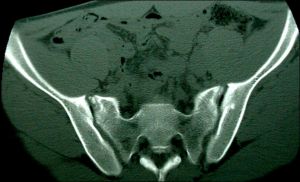

CT圖像是層面圖像,常用的是橫斷面。為了顯示整個器官,需要多個連續的層面圖像。通過CT設備上圖像的重建程式的使用,還可重建冠狀面和矢狀面的層面圖像,可以多角度查看器官和病變的關係。

CT檢查常稱為平掃或非增強掃描,指未行靜脈內注射造影劑或造影的掃描。一般常規先行平掃。腹部及盆腔普通掃描通常在掃描前口服一定量的對比劑充盈胃腸道,以增加胃腸等空腔臟器與周圍組織結構的對比度。

三、 腹、盆腔:各種實質器官的腫瘤、外傷、出血,肝硬化,膽結石,泌尿繫結石、積水,膀胱、前列腺病變,某些炎症、畸形等;